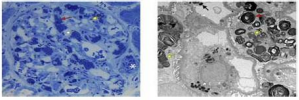

Um paciente de 32 anos de idade foi diagnosticado, recentemente, com hipertensão de diagnóstico (PA = 160 mmHg x 90 mmHg) e hematúria microscópica repetida e confirmada. Exames complementares revelaram creatinina sérica = 1,0 mg/dL e proteinúria na urina de 24 horas = 650 mg. Ele foi submetido a biópsia renal, segundo a figura apresentada, que confirmou o diagnóstico de nefropatia por IgA com pontuação MEST-C M1, E1, S1, T1, С.

Após três meses, o nível da creatinina sérica do paciente piorou gradualmente para 1,5 mg/dL (TFGe = 43 mL/min/1,73 m²), e a proteinúria aumentou de 0,65 g para 2,1 g na urina de 24 horas. O índice de massa corporal (IMC) é de 24 kg/m², a pressão está controlada, e ele não apresenta outras comorbidades. Com base no exposto, qual é o próximo passo?

Qual é o primeiro passo no manejo clínico desse paciente?